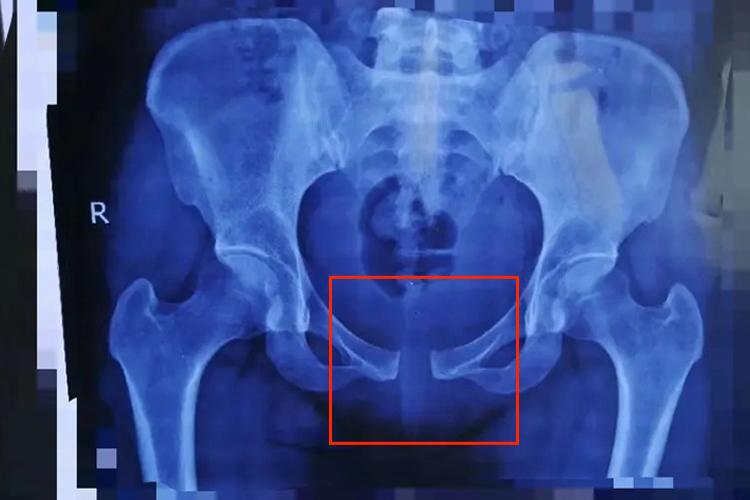

另外,女性的盆骨遭受由后向前的外旋暴力后,也可导致耻骨联合分离,影像学可显示耻骨联合缝隙增宽,甚至>2.5cm,还可伴随骶棘韧带断裂或坐骨棘骨折,以及骶髂前韧带断裂等。